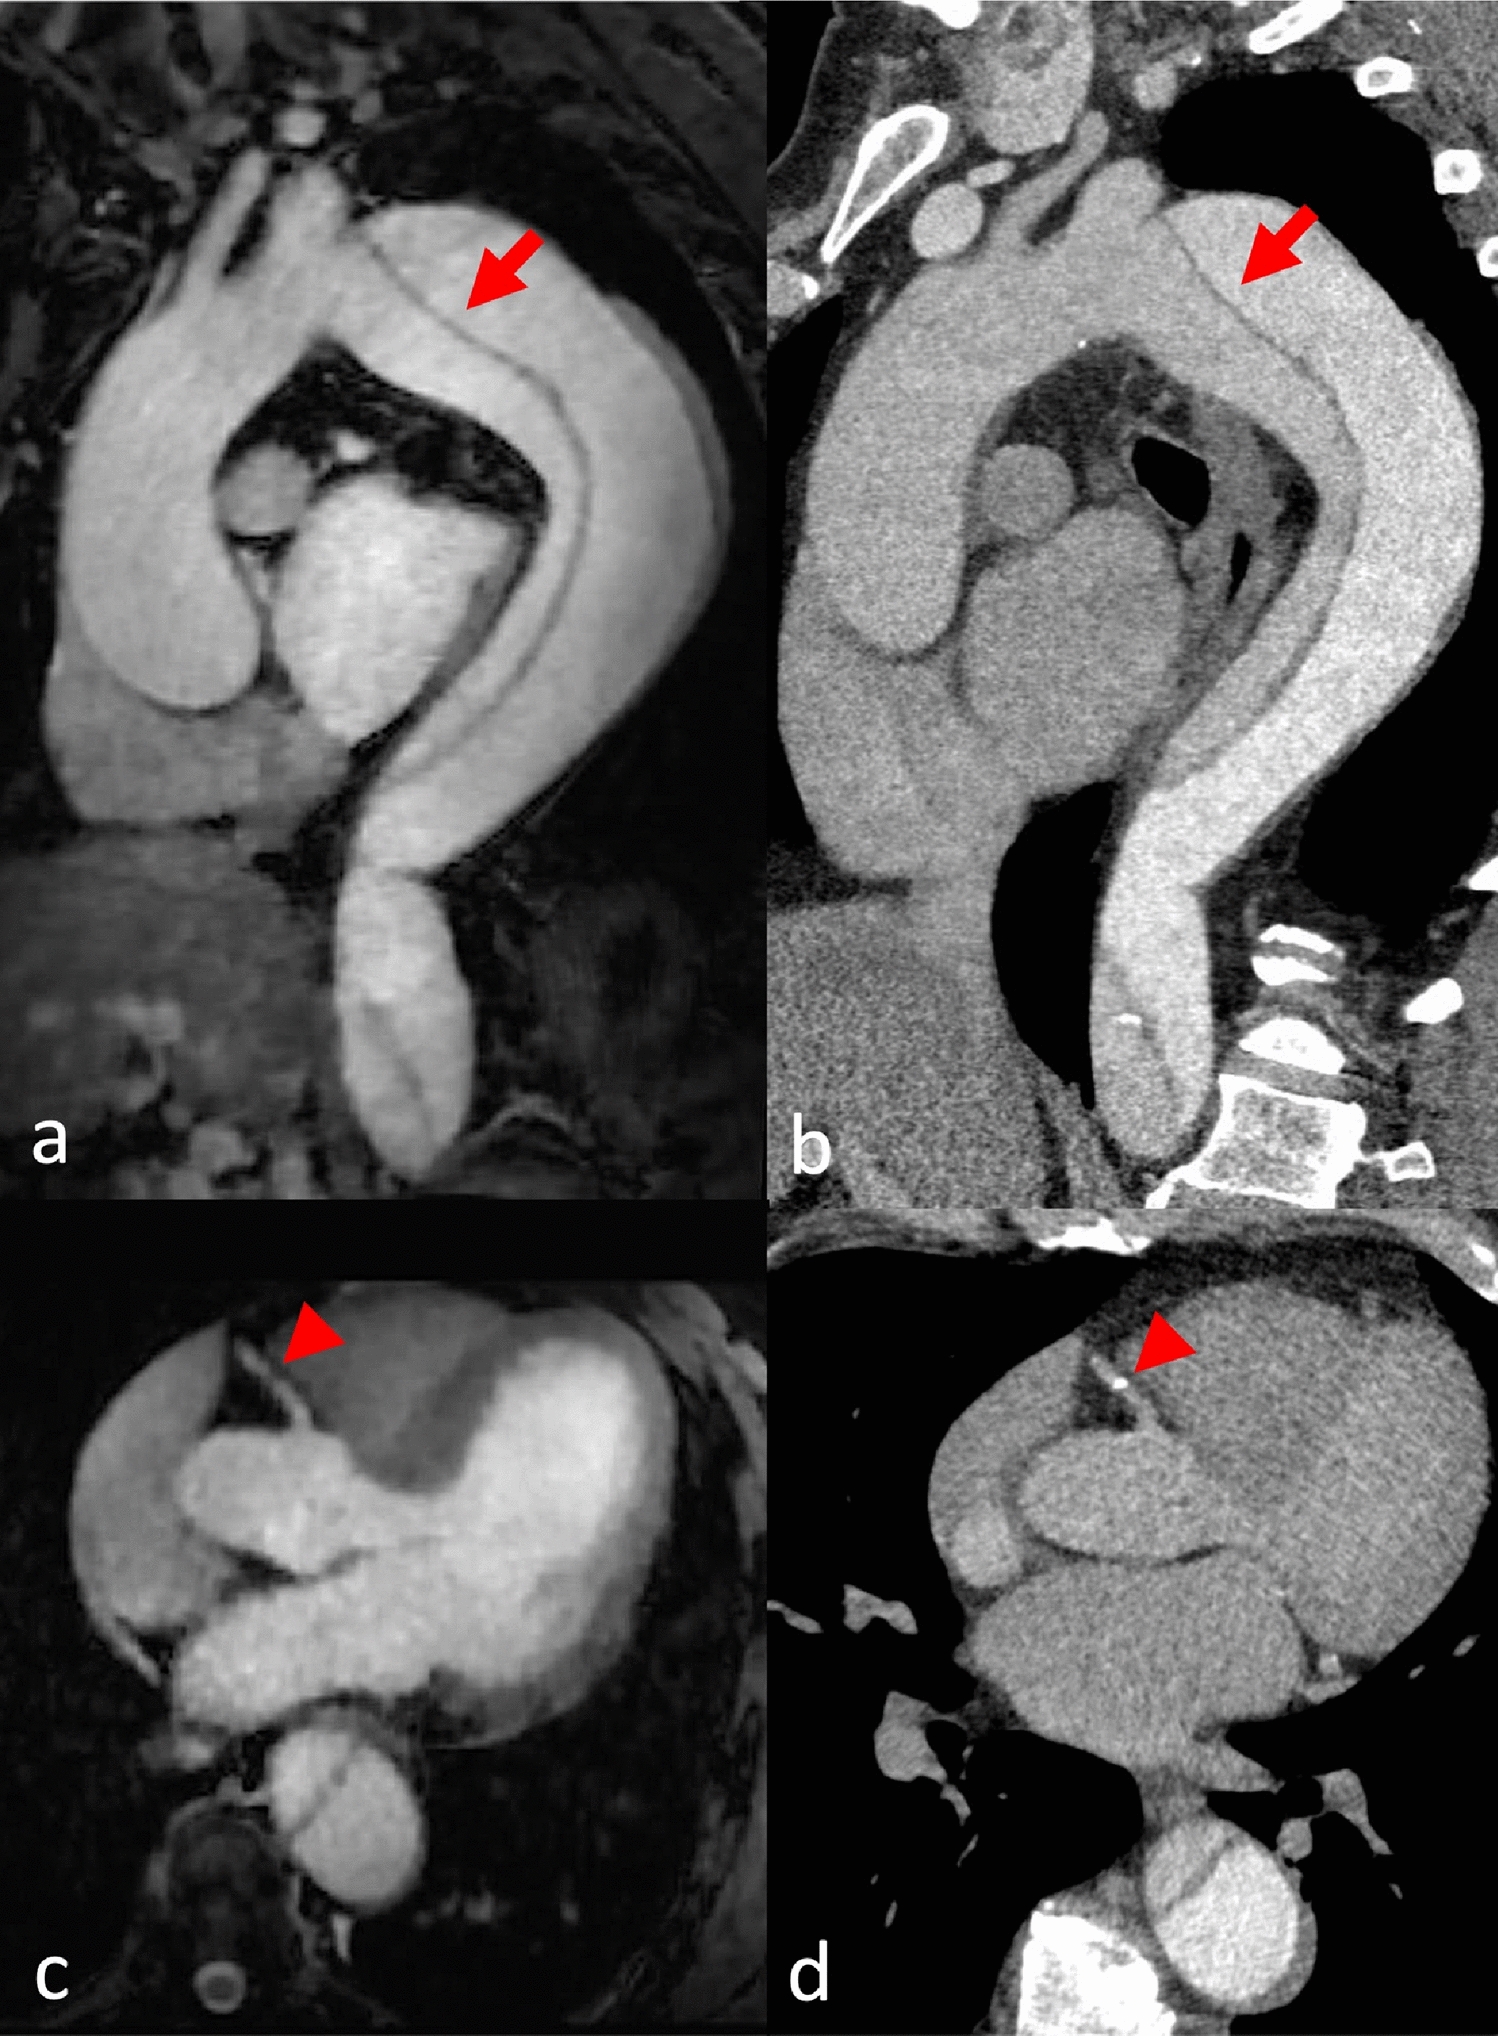

Fig. 5

A patient with Stanford B aortic dissection was scheduled for follow-up imaging. Sagittal (a, b) and axial (c, d) reformations of MRA (a, c) and CTA (b, d). Good depiction in both modalities with unusual bolus timing in the CTA (a) due to a misplaced region of interest in the false lumen (arrow). Flow insensitivity renders both lumina hyperintense in MRA (b). A small calcification was found in the right coronary artery (arrowhead)